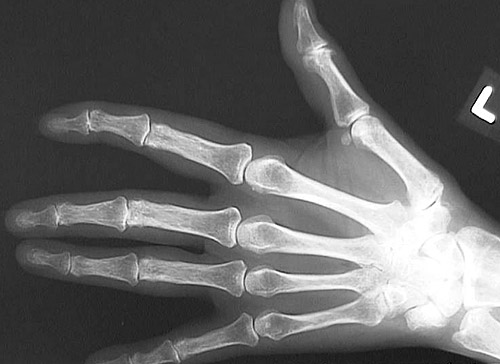

The hand shown here demonstrates features of osteoporosis with rarefaction of bone. There are degenerative changes as well, with subluxation at the DIP joints most marked in the forefinger.